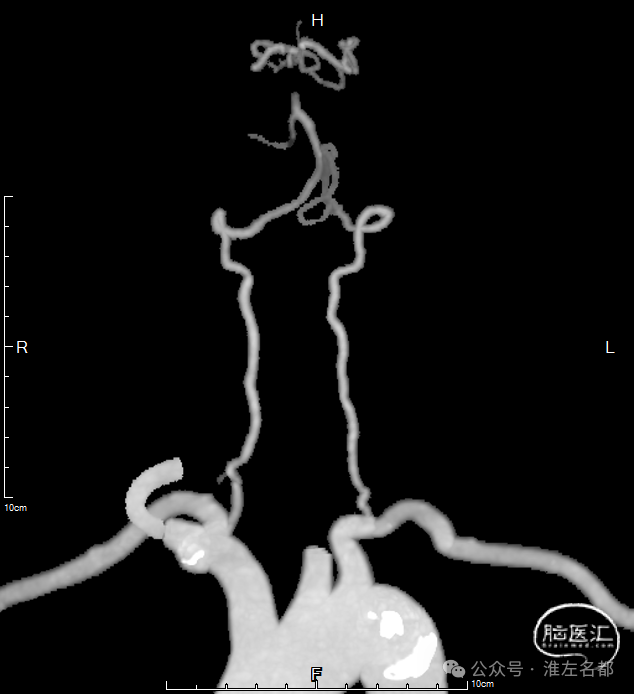

CTA:基底动脉闭塞,双侧胚胎型后交通,基底动脉尖部可见造影剂充盈;弓上血管迂曲明显,双侧椎动脉V1段均见明显曲折,左侧椎动脉颅内段显影不清,但可见右侧椎动脉颅内段延续至基底动脉闭塞近端。

3、根据术前急诊CTA结果,左椎动脉颅内段显影不清,故决定经右椎动脉入路。

4、术前CTA示弓形和弓上血管情况,预测经股穿刺治疗难度不大;出乎所料的是,因右锁骨下动脉迂曲和右椎动脉V1曲折,导致经股路径建立通道难度大,经改变策略尝试失败后,为节约时间,故果断改经桡穿刺。

7、术前CTA示双侧胚胎型后交通,故微导丝和微导管未尝试超选大脑后动脉,微导管头端置于基底动脉远端。